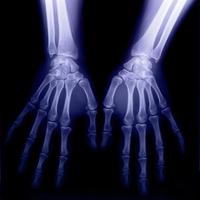

接下來更為神奇的現象發生了,一天晚上倫琴很晚也沒回家,他的妻子來實驗室看他,於是他的妻子便成了在那不明輻射作用下在照相底片上留下痕跡的第一人。當時倫琴要求他的妻子用手捂住照相底片。當顯影后,夫妻倆在底片上看見了手指骨頭和結婚戒指的影象。

這一發現對於醫學的價值可是十分重要的,它就像給了人們一副可以看穿肌膚的“眼鏡”,能夠使醫生的“目光”穿透人的皮肉透視人的骨骼,清楚地觀察到活體內的各種生理和病理現象。根據這一原理,後來人們發明了X光機,X射線已經成為現代醫學中一個不可缺少的武器。當人們不慎摔傷之後,為了檢查是不是骨折了,不是總要先到醫院去“照一個片子”嗎?這就是在用X射線照相啊!